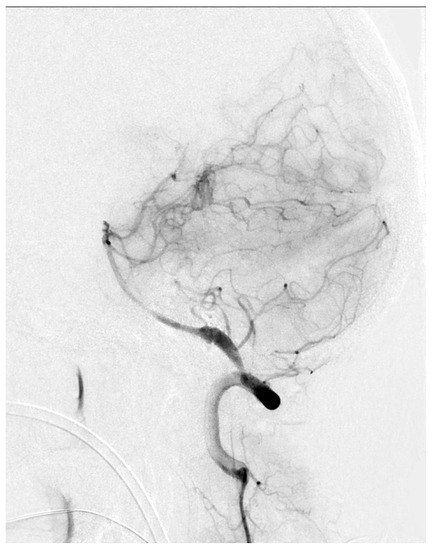

In our study, limb preconditioning prevented vasoconstriction in the mid-basilar artery, but for reasons which are not clear, no effects on the proximal or distal segments were seen. The mid-basilar segment may be more susceptible to vasoconstriction, given that the proximal and distal segments have arterial confluences (vertebrobasilar junction) or bifurcations (top of the basilar), which may confer a more stable vascular structure. We were not able to find clinical reports showing a susceptibility of the mid-basilar artery to vasospasm in human SAH. However, Figure 5 shows a catheter angiogram of a case of mid-basilar vasospasm in a patient with recent SAH, with sparing of the proximal and distal segments.

Figure 5.

Lateral view of basilar artery catheter angiogram in a patient with recent subarachnoid hemorrhage demonstrating mid-basilar artery vasospasm.